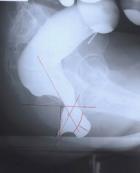

恥骨直腸肌綜合征(puborectalis syndrome)是一種以恥骨直腸肌痙攣性肥大,致使盆底出口處梗阻為特征的排便障礙性疾病。組織學(xué)改變以恥骨直腸肌肌纖維肥大為特征。